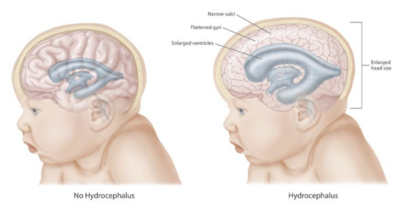

استسقاء المخ Hydrocephalus، هو تراكم السائل الدماغي الشوكي داخل المخ.[1] يتسبب هذا في ارتفاع الضغط داخل الجمجمة. قد يعاني كبار السن المصابين باستسقاء المخ من الصداع، ازدواج الرؤية، عدم الاتزان، سلسل البول، تغيرات في الشخصية، أو التخلف العقلي. لدى الرضع، قد يؤدي استسقاء المخ إلى زيادة في حجم الرأس. وتتضمن الأعراض الأخرى القيء، الأرق، النوبات، والشخوص بالعينين لأسفل.[1]

تراكم السوائل يمكن أن يحدث ضغطاً على الدماغ مما قد يؤدي إلى أعراض عصبية مثل التشجنجات، إعاقة ذهنية ونوبات صرع. هذة العلامات تظهر على نحو مبكر عند الكبار لأن جمجمتهم لا يمكنها التوسع لاستيعاب الحجم الزائد للسائل النخاعي. في الأجنة والرضع والأطفال الصغار الذين يعانون من استسقاء الرأس، سيحدث عندهم توسع وانتفاخات في رأسهم دون تأثر عظام الوجه، وذلك لأن عظام الجمجمة لم تلتحم مع بعضها بعد. هناك علامة أخرى تحدث عند الأطفال وهي ثبات النظرة التحتية مع بياض العين الذي يظهر فوق القزحي، على الرغم من أن الأطفال كانو يحاولون فحص الجفن السفلي الخاص بهم.[12]

إذا كانت الفتحة في البطين الرابع أو القناة الدماغية قد أغلقت، فإن السائل النخاعي سيتراكم في البطينات. تسمى هذه الحالة استسقاء الرأس الداخلي ويسبب هذا ارتفاعاً في ضغط السائل النخاعي. انتاج السائل النخاعي سيستمر، حتى لو كان هناك إغلاق في امتصاص السائل النخاعي إلى الدورة الدموية خارج الدماغ. وبالتالي، السائل النخاعي سيتراكم داخل الدماغ، مسبباً بذلك توسع البطينات الدماغية وضغط على النسيج العصبي. عادة يؤدي الضغط على النسيج العصبي إلى تلف لا يمكن استرجاعه. إذا لم تكن عظام الجمجمة قد أكملت تحجرها والتحامها أثناء حدوث استسقاء الرأس، فإن توسع الرأس بشكل كبير سينتج من ارتفاع الضغط أيضاً. القناة الدماغية يمكن أن تكون مسدودة عند وقت الولادة أو تنسد في وقت لاحق في الحياة بسبب نمو ورم في جذع الدماغ.

في الأطفال الذين يعانون من استسقاء الرأس، السائل النخاعي يتراكم في الجهاز العصبي المركزي مما يتسبب في انتفاخ اليافوخ (بقعة لينة)، والرأس يصبح حجمه أكبر مما هو متوقع. ومن الأعراض التي يمكن أن تظهر في وقت مبكر: